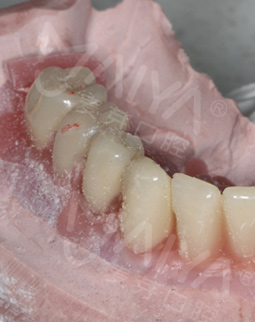

麦芽的博士专家团在看过我的片子后发现,我的牙齿由于长期对口腔疏于护理,牙周情况非常差,余牙有些松动,且牙槽骨萎缩严重,现存的骨量无法进行传统的种植牙手术,因此给我设计了“all-on-4”种牙技术的升级版本“all-on-5”,前期是要处理我的牙周问题,当天就给安排了洁牙,然后上药,等牙周恢复差不多就可以进行种植了!

经过一个月的牙周治疗,牙齿肿胀部分都已经消退,来麦芽种牙之前,心理还有点小紧张,总害怕种牙特别疼,恢复时间慢。我的牙齿情况比较复杂,部分牙齿有牙槽骨吸收,经过前期的各种检查,医生说我的身体状况适合种牙。

但是打完麻药,躺在那里发现手术时一点感觉也没有,半口牙只种了5颗牙钉,而且不到一个小时,感觉自己就眯了一会就好了。麦芽的种植专家们手法特别棒,很稳。牙钉种好之后,没有立即戴牙冠,医生用硅橡胶取模,为我制作了临时牙冠,不过看到临时牙冠我就能想象到完全种好牙的样子了!然后,医生给我一个小卡片,上面记录了种牙后的注意事项,告诉我种完牙后自己维护也很重要。医生说要按时复诊,也会有专门的工作人员进行通知,不得不说麦芽在细节上真的很暖心。